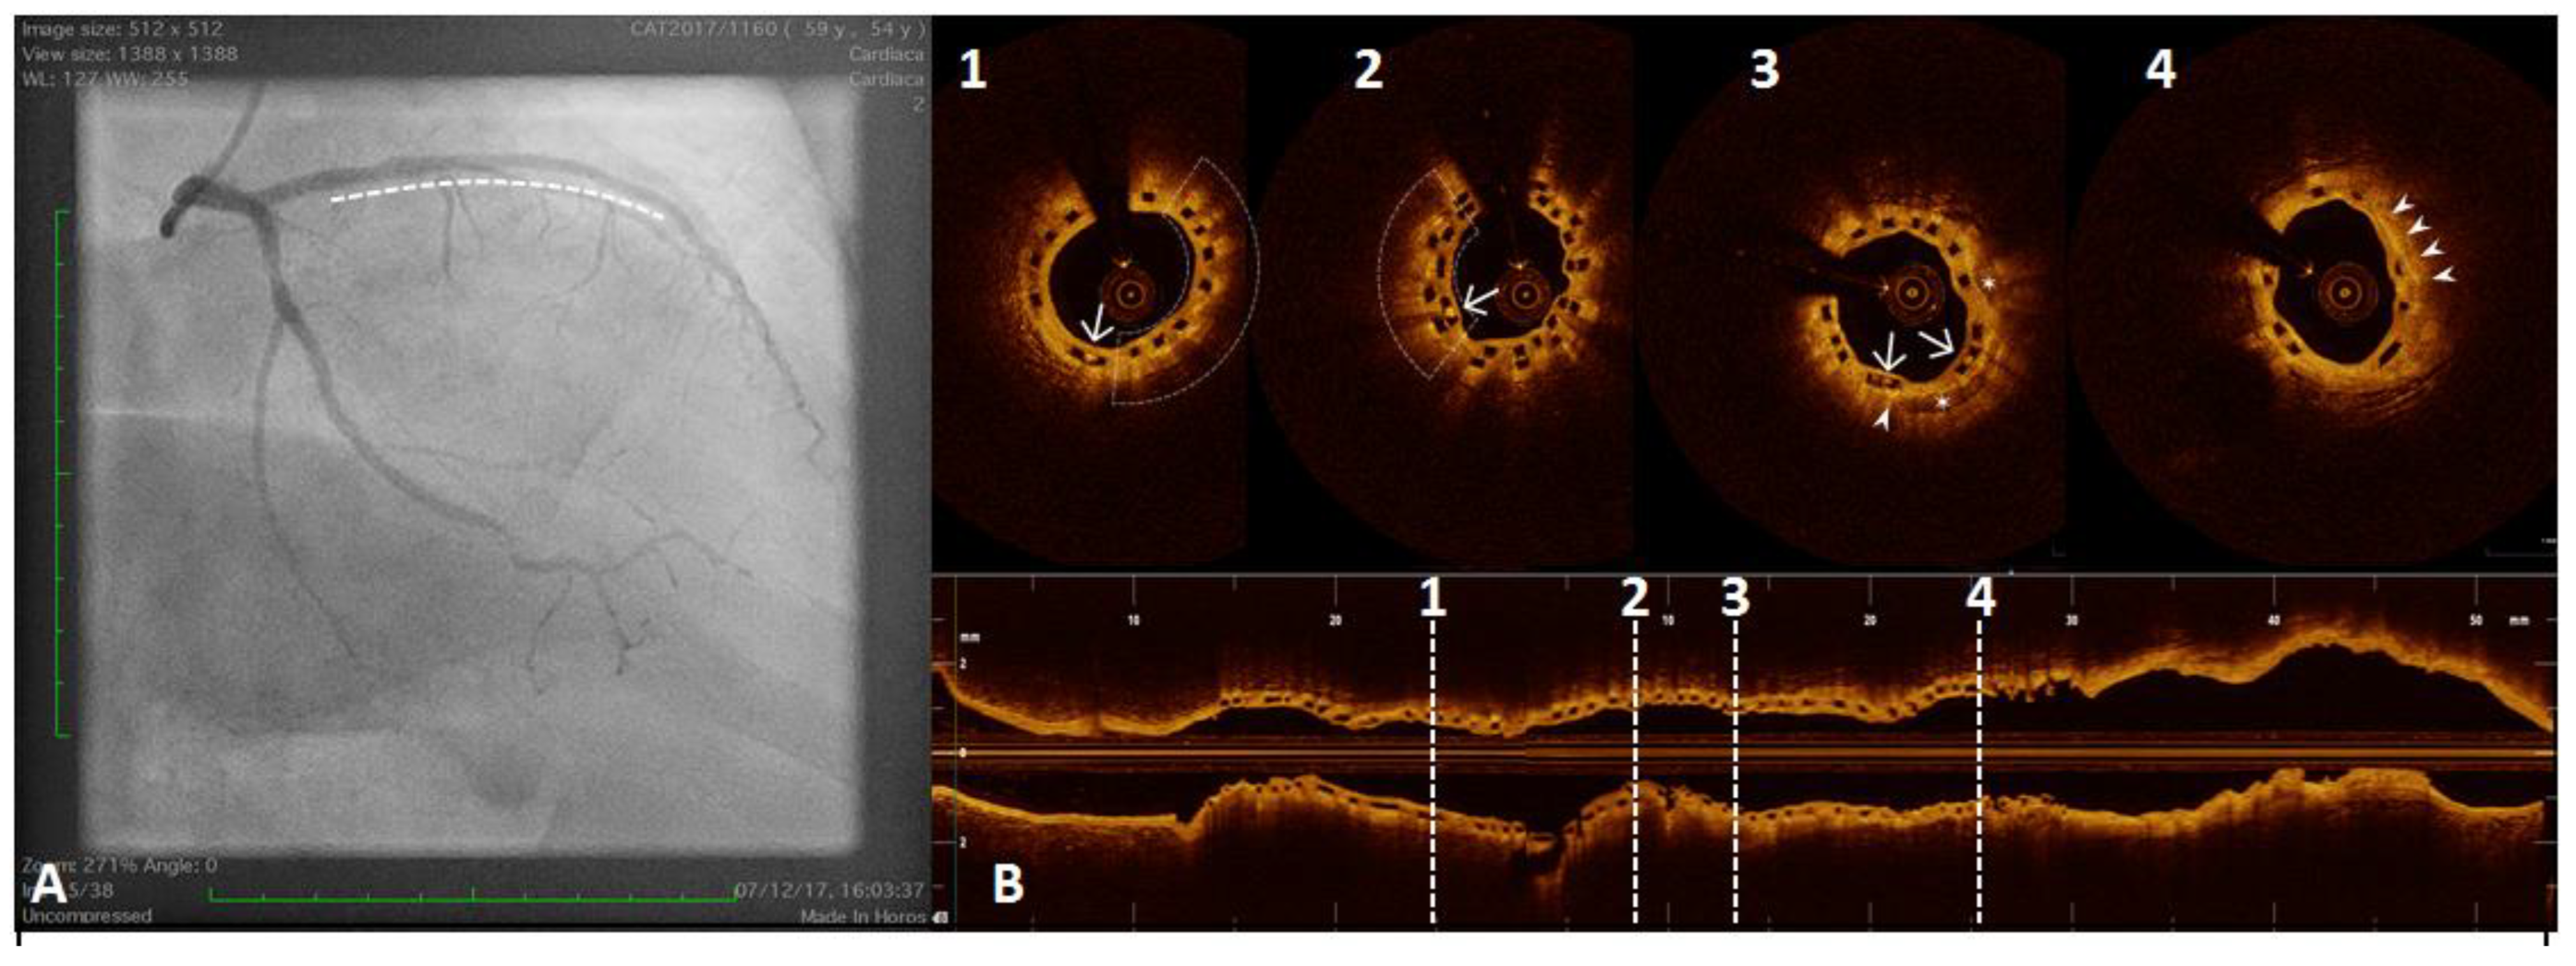

Figure 5.

A 61 year old man referred for Non-ST-segment elevation myocardial infarction (NSTEMI). Coronary angiography showed no significant coronary lesions. Left circumflex showed haziness at the proximal segment (panel (A), white arrow). The OCT pull-back showed a fractured plaque (panel (B), 1, white arrow) associated with a lipid pool (panel (B), 1 and 2, “L”); thin-cap fibro-atheroma and active macrophages are easily detected because of their typical bright line (2, white arrows) or spot images, within a fibro-lipidic plaque (3, white arrows).

Figure 6.

A 54 year old woman after a scheduled angiogram and OCT pull-back 3 years after an acute coronary syndrome. During index procedure 2 bioresorbable vascular scaffolds (BVS) were implanted. Coronary angiography showed satisfactory angiographical result (panel (A), white line). OCT pull-back confirmed a complete struts coverage and an acceptable lumen area (panel (B)), even at the overlapping site (2). Black boxes are typical OCT images of BVS (1,2,3 and 4). Some black box inclusions are detected (1,2 and 3 – white arrows) representing scaffold reabsorption processes. Some areas immediately below the boxes showed bright spots indicating inflammation with macrophages activation (1 and 2 - underlined area). These bright spots (3 and 4, white triangle) have been detected closely to calcium arch (3, stars) and in a fibro-lipidic plaque (4).